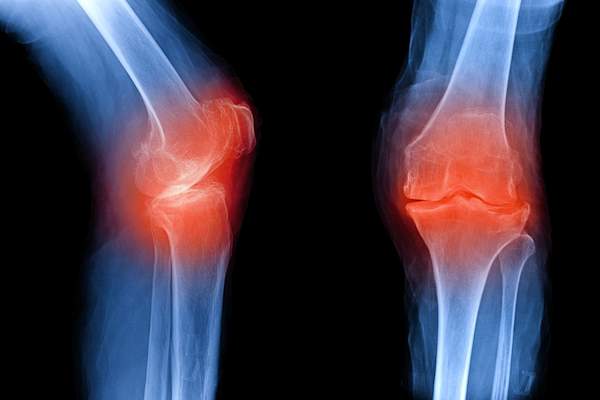

OA影响负重关节(+手)

罗宾逊博士说,如果你在年轻的时候经历过关节的任何创伤或损伤,那么它可能会在几年后发展成OA。但最常见的关节是膝盖、臀部和脊柱的承重关节,加上手——通常是指尖关节或中指关节,或拇指底部。在髋关节和膝关节,OA通常是不对称的,影响一侧或另一侧,克利夫兰大学医院风湿病学部主任Ali Askari医学博士说。

OA的症状包括关节疼痛

随着OA,软骨的解体引发的化学物质,引起疼痛的版本说,阿斯卡里博士,但通常没有太大的发红,发热或肿胀。(If you notice enlargement in your finger knuckles, that’s likely a bony growth, not swelling, says Dr. Askari. ) The pain may feel “achy” or “throbbing” and typically acts up with movement, getting worse toward the end of the day, says Dr. Askari. Many OA patients also experience joint stiffness after waking up in the morning, or after sitting for prolonged periods, but that usually fades within 30 minutes, says Dr. Ashany.